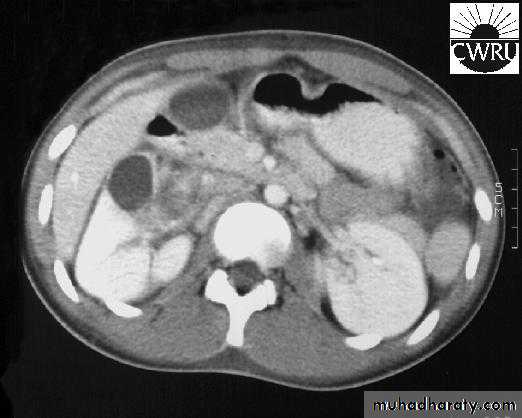

CT scan: right renal abscess

CT scan: Left renal abscess

CT scan & MRI: diagnostic.